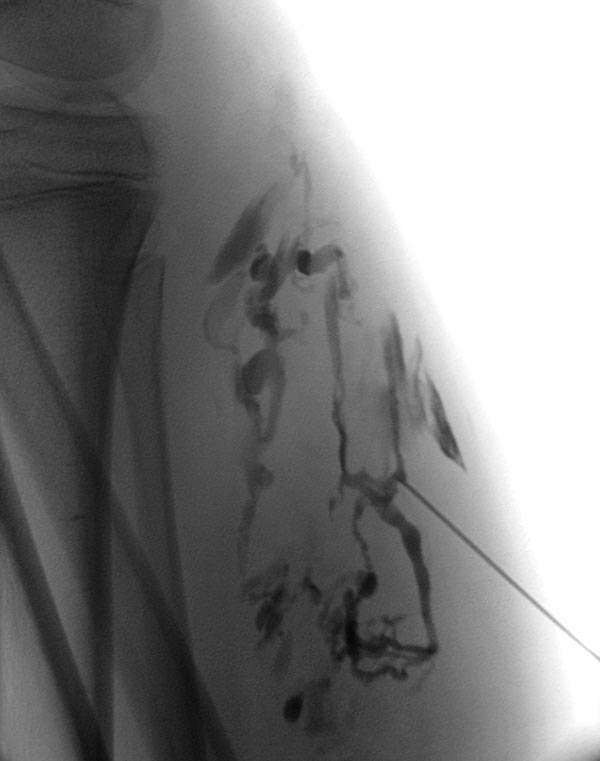

Die Phlebographie nach Direktpunktion des venösen Malformationsanteils zeigt eine großlumige Drainagevene, die in der Kniekehle mit der V. poplitea kommuniziert. Diese muss zunächst verschlossen werden, da sonst das Sklerosierungsmittel darüber abfließen könnte und potentiell eine Thrombose der tiefen Leitvenen des Beins (und eine Lungenembolie) verursachen könnte. Zudem besteht grundsätzlich ein erhöhtes Thrombembolierisiko bei der Patientin, dass durch den Verschluss deutlich vermindert werden kann.

Dazu wird zunächst über einen Einführungsdraht eine großlumige Einführungsschleuse vorgebracht, die zum Einführen der Laserfaser dient. Dieser wird über die Vene bis zum Kommunikationspunkt in der Kniekehle vorgeschoben.

Durch diese Schleuse wird eine Laserfaser zur endovaskulären Lasertherapie vorgeführt. Durch die Erhitzung des Laserstrahls kommt es zu einer massiven Reizung der Venenwand, die sich anschließend sehr schnell verschließt. Um die Laserspitze kommt es sofort zur Thrombusbildung (weiß, da als Kontrastmittelaussparung sichtbar).

Nach Verschluss durch die Laserfaser und Anspritzen über die zurückgezogene Schleuse kommt es nicht mehr zu einem Abstrom des Kontrastmittels über die Kommunikationsvene, die erfolgreich verschlossen ist. Es kontrastiert sich nur noch die venöse Malformation. Diese ist jetzt bereit zur Sklerosierungsbehandlung, da dieses nicht mehr abfließen kann.